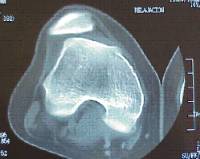

Osteocondritis dissecant

És una patologia ocasionada per una isquèmia transitòria de l’os subcondral i pot progressar fins a arribar a desprendre’s.

Es localitza amb més freqüència al còndil femoral intern i el seu pronòstic varia en funció de l’edat de presentació (poc freqüent per sota dels 10 anys) i l’estabilitat de la lesió.

El tractament passa per limitar l’activitat esportiva d’impacte, variar l’eix de càrrega mecànic de l’extremitat i, potser, dur a terme una intervenció quirúrgica.

Hi ha diferents opcions de tractament quirúrgic en funció de l’estabilitat i localització del fragment osteocondral (microperforacions sota control artroscòpic, fixació in situ del fragment osteocondral, ús d’empelts osteocondrals/mosaicoplàstia).

En els casos evolucionats amb despreniment del fragment osteocondral, cal retirar el cos lliure articular ("ratolí" articular).